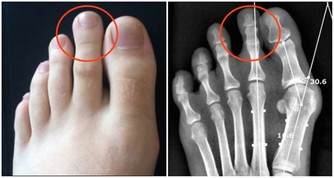

其一,如果是齲齒引起的牙疼,會造成牙齒的咀嚼效率下降,牙疼會愈演愈烈。如果不及時補牙,就有可能引起牙髓炎、根尖周炎等牙髓疾病。

當形成牙髓疾病之後,患者會感受到難以忍受的劇烈疼痛。尤其是在夜晚,疼痛會加劇,如吃藥也只能暫時緩解,幾天後又會復發。對於耐受力較差的老年人,會加重頭痛、心臟病、糖尿病等疾病,甚至會引起中風。

其二,牙疼也有可能引起牙周疾病。它是一種緩慢的破壞性疾病,患者如不及時接受治療,是有可能引起牙齒鬆動,甚至脫落,對日後的進食和咀嚼都造成不利的影響。